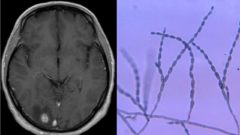

Migrény, paralýza tváre

Migrény, paralýza tváre i porážka. Mužovi žije v mozgu vzácna čierna pleseň, ako jeden z mála s ňou ešte žije